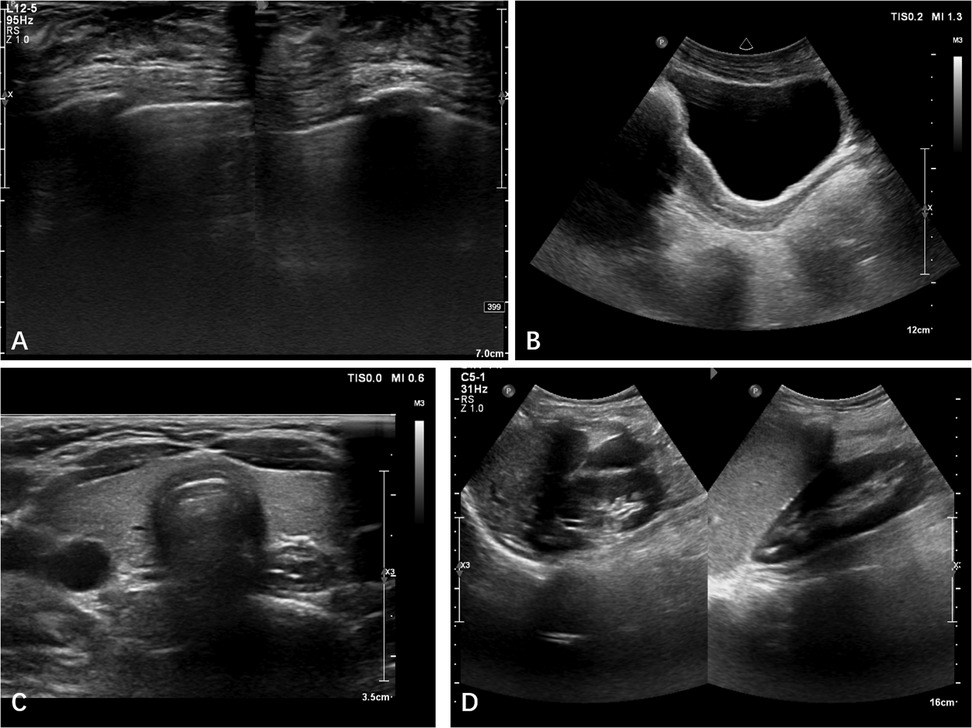

The patient, a 14-year-old female, experienced a fall while running. Initially, she complained of left leg and ankle pain and was unable to bear weight. However, she did not seek medical attention and continued with the weight-bearing activities, and her parents didn't notice the abnormality. After three months with persistent symptoms, she presented to a medical institution where an x-ray revealed a distal tibiofibular fracture. She underwent two months of cast immobilization followed by one month of external fixator fixation. No specify drug was intaken during this period. Follow-up x-rays showed nonunion at the fracture ends. Then she visited our outpatient clinic. Physical examination revealed facial asymmetry, multiple café-au-lait spots over her body, breast development, approximately 10° external rotation deformity of the distal left leg, limited active movement of the left ankle with pain on passive movement, and inability to bear weight independently (Figure 1). Comprehensive x-rays and CT scans identified nonunion of the left distal tibiofibular fracture in addition to the abnormal bone structure in the bilateral femurs, tibiae, left parietal bone and left mandible (Figure 2). Ultrasound revealed bilateral breast enlargement (Figure 3A) and enlarged uterus (Figure 3B), while thyroid (Figure 3C) and adrenal glands (Figure 3D) showed no abnormalities. Hematological hormone tests were normal (Table 1), as were whole exome sequencing tests, which showed negative results. Based on clinical examination and laboratory findings, she was diagnosed with MAS.

Figure 3. Ultrasound revealed bilateral breast enlargement (A) and enlarged uterus (B), while thyroid (C) and adrenal glands (D) showed no abnormalities.